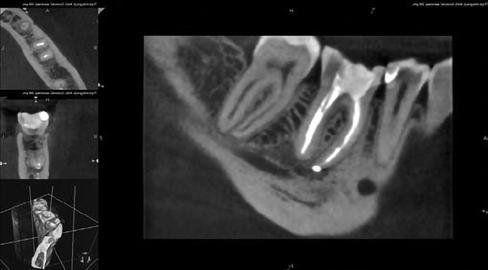

A pácienst a jobb alsó első nagyőrlőfog (46) nem sebészi endodonciai ellátása céljából irányították dr. Karaś rendelőjébe. A fog panaszos volt, valamint röntgenfelvételen a mesialis gyökércsúcs körül periapikális gyulladás jelei voltak észlelhetők. Míg a gyulladásra utaló jelek egyértelműen észlelhetőek voltak, addig a gyökércsatorna formája csak nehezen volt felismerhető (22. ábra). Ennek megfelelően CBCT-felvétel készült, amelyen jól látható volt a mesiobuccalis csatornában kialakult belső reszorpció, valamint egy csatornaszű-

kület és a meziális gyökér csúcsát érintő gyulladásos reszorpciós folyamat (23. a–b. ábra). Ezen felül a fogban egy öntött csap volt látható, valamint a fogat fémkerámia korona borította.

Az első megbeszélés során a páciensnek két terápiás alternatívát ajánlottunk fel. Az egyik a fog sebészi újrakezelése, a másik pedig a fog nem-sebészi újrakezelése volt. Szájüregi vizsgálatot követően megállapítottuk, hogy a korona minősége már nem mutatkozott megfelelőnek és mindenképp cserére szorul (24. ábra). A lehetőségek figyelembevételével a korona eltávolítása és nem-sebészi endodonciai terápia alkalmazása mellett döntöttünk.

A terület érzéstelenítését követően a koronát egy gyorsító segítségével kettévágtuk (25. ábra), majd eltávolítottuk. Ezt az öntött csap eltávolítása (26–27. ábra), a pulpakamra és a maradék foganyag vizsgálata követte. Sérülésekre vagy repedésekre utaló jeleket kerestünk. Mivel mindent rendben találtunk, ezért gingivectomia (28. ábra) végzését követően felhelyeztük a kofferdámot (29. ábra). Az izolálás minőségét folyékony kofferdám segítségével növeltük (30. ábra). Miután meggyőződtünk az izolálás megfelelőségéről, adhezív protokoll alkalmazása mellett (6. generációs önsavazó adhezív és bond) elvégeztük az endodonciai csonkfelépítést (31. ábra). A gyökértömő anyag és a cement maradványait gyémántbevonatú ultrahangos fej segítségével távolítottuk el (Woodpecker) (32. áb-

ra). A gyökércsatornák teljes hosszát végig tudtuk szondázni kézi tűk segítségével (VDW). A csatornák tágítását martenzites gépi gyökérkezelő tűk segítségével végeztük 40/.04 méretig (Poldent). A megmunkálás során a gyökércsatornák EDTA tartalmú krémmel voltak feltöltve (VDW, 33. ábra). Az egyes eszközök között a csatornákat 5,25%-os NaOCl-oldattal (Cerkamed) öblítettük át. A végleges méret elérését követően a végső átöblítési protokoll részeként háromszor átöblítettük 5,25%-os NaOCl, és 40%-os citromsav oldattal, amit ultrahangos eszközökkel (MANI) aktiváltunk, majd végül a teljes gyökércsatorna-rendszert ismét 5,25%-os NaOCl-lel töltöttük fel, amelyet 10 percen keresztül aktiváltunk ultrahanggal (34–35. ábra). Ezt követően jól megfigyelhető volt az átöblítőszerek mezialis csatornák között történő áramlása. A kezelés kritikus pontra érkezett. Döntést kellett hozni a mezialis gyökérben lévő rezorpcióval és szűkülettel kapcsolatban. Egyrészt a nem penetráló belső rezorpció ellátása során az elsődlegesen választandó terápiát sealer és guttapercha együttes alkalmazása jelentené. Másrészt a gyökércsúcsnál lévő gyulladásos reszorpciós elváltozás ellátásához MTA vagy egyéb sűrű konzisztenciával rendelkező anyag használata lenne előnyös. Általában nem jelent gondot ennek a két anyagnak az egy gyökéren belül történő alkalmazása, azonban ebben az esetben rendkívül szűk csatornákkal álltunk szemben, ahhoz, hogy minden fenntartás nélkül lehessen MTA-t alkalmazni, valamint a szűkület jelenléte is további kérdéseket vetett fel.

A fenti nehézségek megoldására jó ötletnek mutatkozott egy trikalcium-szilikát alapú sealer használata. A sealert az előbbiekben ismertetett módon juttattuk be a gyökércsatornákba. Az előre bekevert sealert tartalmazó fecskendőre (META BIOMED) egy kanült helyeztünk, amelyet bevezettünk a mesiobuccalis csatornába, majd enyhe nyomást ki-

fejtve a csatornába injektáltuk az anyagot, mindaddig, amíg azt nem észleltük, hogy a mesiolingualis csatornában megjelenik a sealer. A disztális csatornát ezt követően töltöttük fel. Ezután minden gyökércsatorna-bemenetnél enyhén felmelegített guttaperchából egy kis dugót képeztünk, amelyet kézi pluggerekkel finoman belenyomtunk a csatornákba. A gyökértömés elkészítését követően kontroll röntgenfelvételt készítettünk. A biokerámia sealer enyhén túljutott a rezorpció által érintett gyökércsúcson (36. ábra). Ezután megtisztítottuk a pulpakamrát (37. ábra) és üvegszál-erősítésű anyag segítségével csonkfelépítést végeztünk, majd eltávolítottuk a rózsaszín kompozitból készült ideiglenes felépítményt. Ezt követően a pácienst visszairányítottuk beutaló orvosához végleges protetikai restaurátum készítése céljából.

A páciens három év múlva érkezett kontrollra. A kontroll röntgen és a CBCT-felvétel is a periapikális lézió eltűnését igazolta. A biokerámia sealer nem szívódott fel és a fog mindvégig panaszmentes volt (38. ábra).